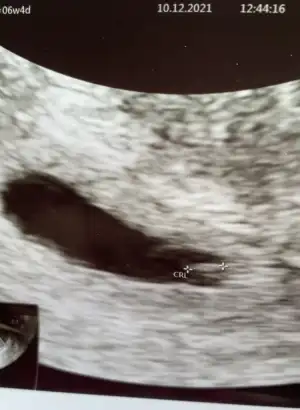

Ben de bugün kontrole gittim 6+4 teyiz 3 mm olmuşuz kalbimiz de atıyor çok şükür 🤲🏻❤️ Üstümden büyük bir yük kalktı ☺️ Foti de koyiyim bu haftada cinsiyet tahmini yapılıyomuş belki fikri olan olur 🤣